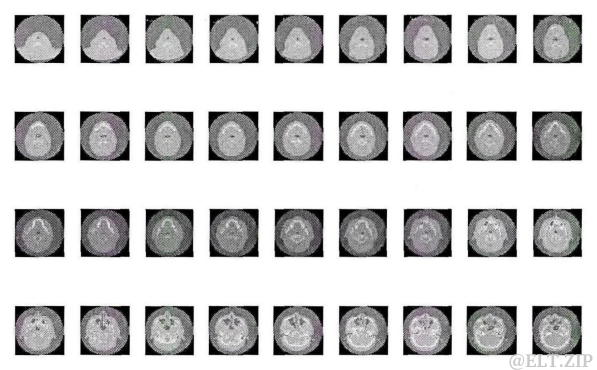

医学序列图像是指在相同的成像设备下,对同一研究对象,在不同断层的扫描切片集合或不同时间的扫描切片集合。根据切片集合的不同来源,可分为

时间序列图像和空间序列图像。时间序列图像是指患者延时间轴获得的图像集,记录患者在一段时间内的病患信息,例如,一位SARS病人在发病期间,每天都要拍摄胸腔CT影像,这些在时间上离散的影像,就构成了一组相同类型的医学时间序列图像。空间序列图像是指成像设备对病人某个器官的不同断层的扫描切片,利用这些连续的扫描切片,通过三维重建技术,将人体器官以“三维”的形式真实地显示出来,实现其三维可视化。

图三.医学序列图像示例 -

医学序列图像有其自身的特点,即背景比较单一,序列中相邻的图像包含的大部分信息是相同的, 也就是说表示这些图像会存在大量的重复信息,图三展示了展示了某个病例的部分颅脑 CT 图像序列,可以看出,这些图像序列是渐变的,即

相邻图像的变化很小。因此,本文提出的基于稀疏表示的医学序列图像压缩方法,就是首先减少序列图像之间的相关冗余信息,然后采用稀疏表示的方法压缩图像数据,从而达到图像压缩的目的。

- 从医学序列图像(图三)的特点可以看出,序列中

相邻图像存在很强的相似性,若将图像划分为指定大小的图像块,在这一系列的图像块中,会存在很多相似的图像块。 - 基于此,本文提出基千稀疏表示的医学序列图像压缩方法,首先将一例序列图像分块,然后根据所有图像块之间的相似性,选择一些图像块作为基准块,就是说,其他的图像块与基准块集合中的某一块非常相似,可直接用该基准块来代替。在进行相似性衡量之时,一一记录下所有图像块与基准块之间的对应关系。然后只用对基准块集合进行